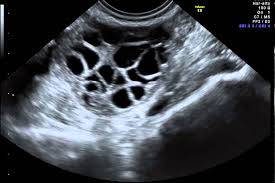

- Ovarios poliquísticos en ecografía: presencia de 12 o más folículos de 2 a 9 mm en corona radiada (en forma de collar de perlas) en cada ovario o de volumen ovárico agrandado (más de 10 ml). Es suficiente que estas características se den en uno de los ovarios.